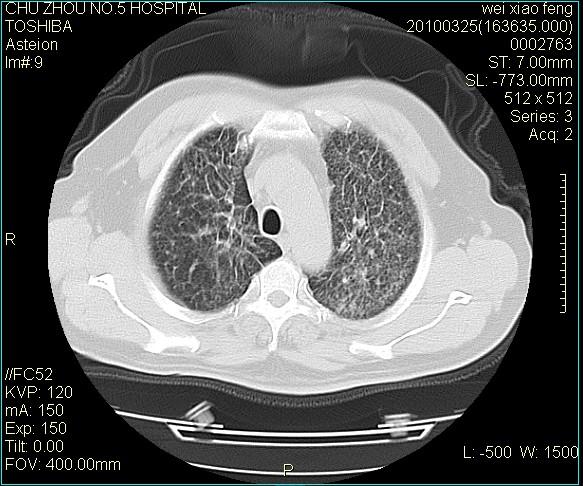

男,60岁,反复咳、痰、喘3月,加重3天。

双肺间质性改变。

考虑双肺血型潘散肺结核/

间质性肺炎伴间质纤维化!不排除伴有职业病!

急性血型潘散肺结核。

双肺间质纤维化,双肺血型潘散肺结核。

考虑间质性肺炎伴间质纤维化。

间质病变,间质炎症,间质纤维化趋势

右肺中叶结节影为原发灶,考虑右肺中叶周围型肺癌并淋巴道转移